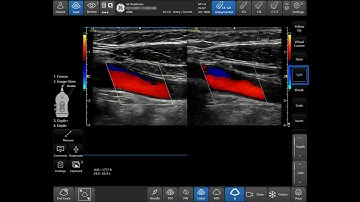

Venue Family Tutorials: Optimizing Color PDI